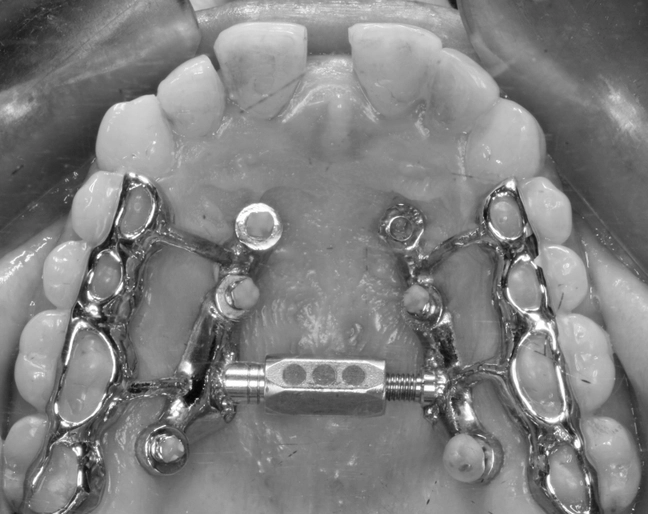

Anclaje esquelético MARPE guiado.

2. E EJECUCIÓN/EQUILIBRIO: Entre la ciencia y la sensibilidad. El ortodoncista moderno vive entre dos mundos: la tradición analógica y la revolución digital. Esta llave enseña a integrarlos. Ni rechazo tecnológico, ni dependencia ciega. EQUILIBRIO es criterio: usar lo nuevo sin olvidar lo esencial. “Lo digital no sustituye al criterio; lo amplifica cuando el juicio clínico está formado.”

MARPE en adultos / Miniplacas Clase III.

3. XCROSS/EXPANSIÓN: La tercera llave es la integración. Cuando biomecánica, cirugía y tecnología se alinean, los límites desaparecen, se amplian las fronteras. Ni la edad ni la complejidad son barreras cuando hay protocolo guiado. Lo que antes era imposible, hoy se resuelve con confianza.